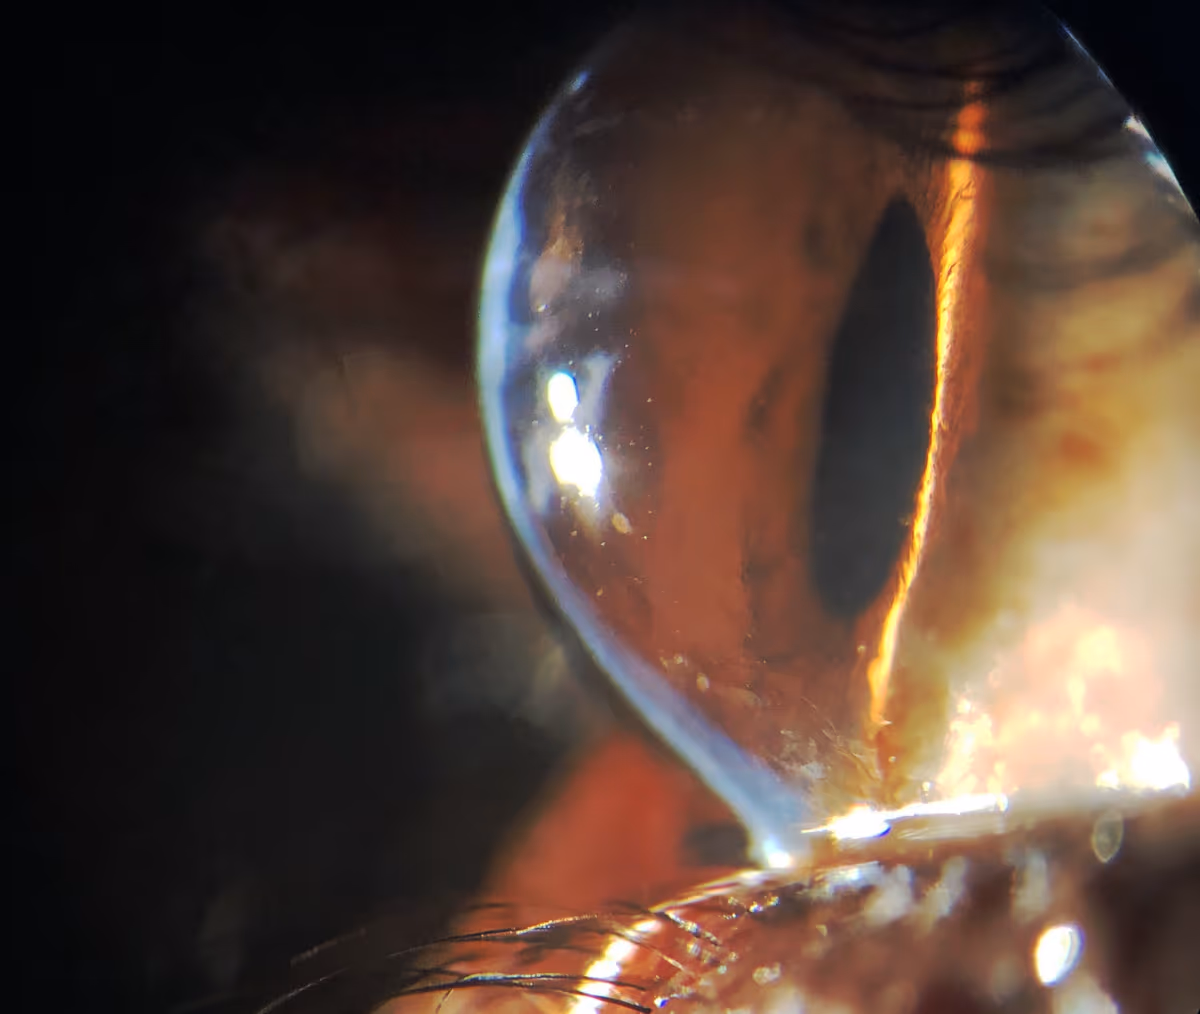

A indicação costuma ser discutida quando exames mostram progressão do ceratocone ou quando o comportamento da córnea sugere risco de progressão.